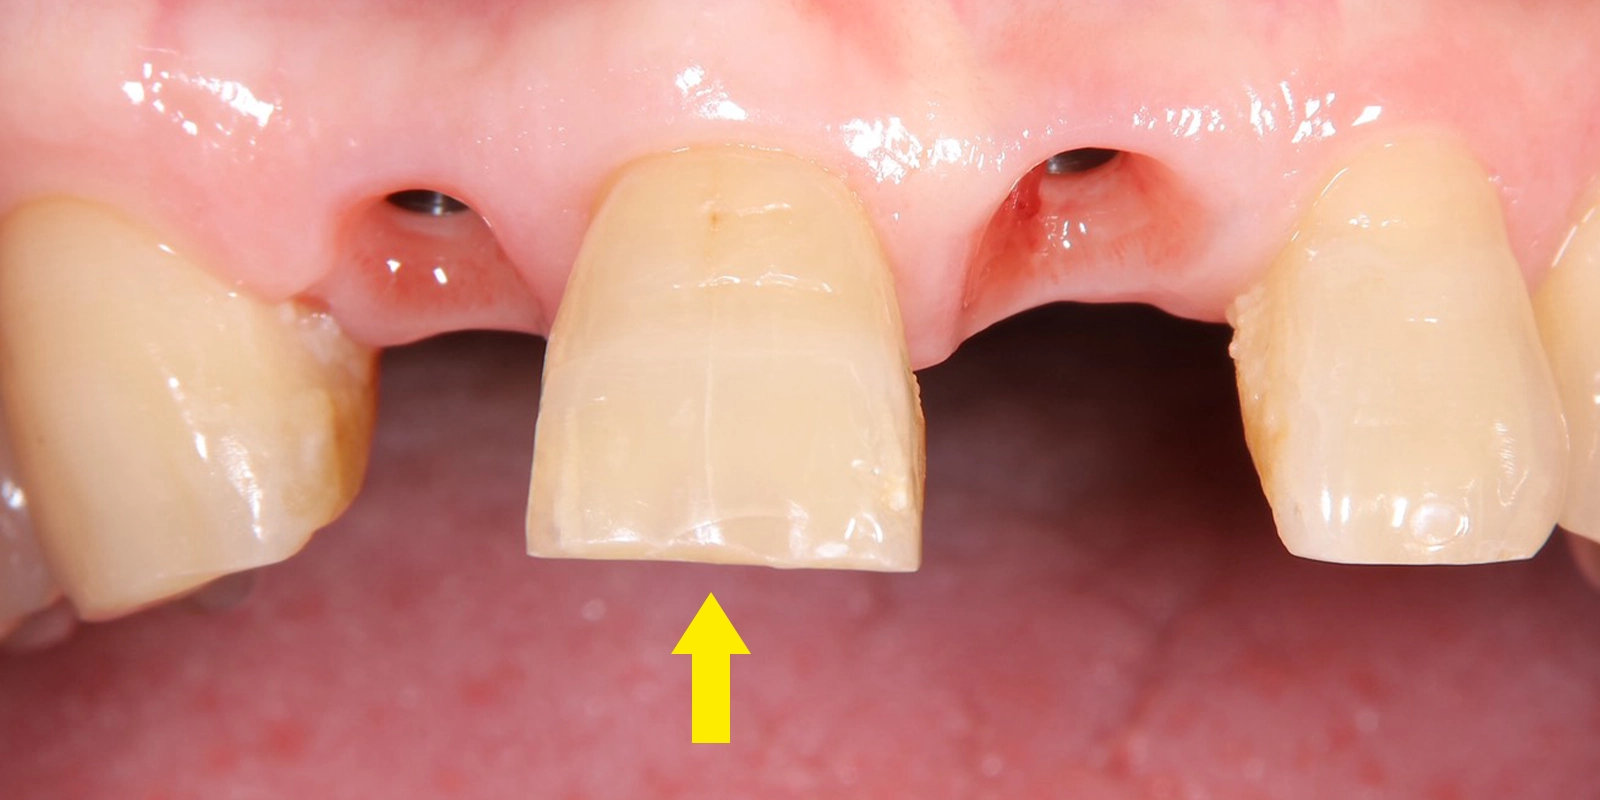

こちらの写真は術後1週間ほど経過した後の様子になりますが、仮歯の状態でも全く問題ございませんでした。

この黄色線がスキャロップ

治療後は隣の歯と光沢が調和した

矢印の中央の歯の色調と

左右のそれぞれの被せ物の色調を揃えた